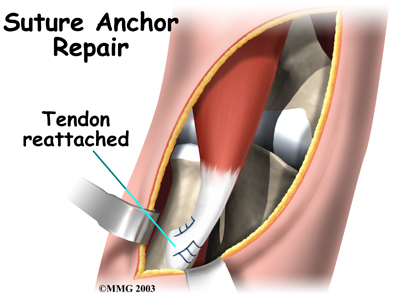

Suture Anchor Method

A new method of anchoring the torn tendon to the radius is gaining popularity. This method uses special anchors, called suture anchors, to fix the tendon in place. The procedure requires only one incision and appears to lessen the risk of myositis ossificans. Myositis ossificans is an abnormal healing response that causes bone to form in the muscles and soft tissues.

A new method of anchoring the torn tendon to the radius is gaining popularity. This method uses special anchors, called suture anchors, to fix the tendon in place. The procedure requires only one incision and appears to lessen the risk of myositis ossificans. Myositis ossificans is an abnormal healing response that causes bone to form in the muscles and soft tissues.

The surgeon begins by making a across the arm, just above the elbow. Along the outside edge of the arm, the incision curves and goes upward for a short distance. The skin and underlying tissues are pulled back using retractors. This reveals the front of the lower biceps muscle and allows the surgeon to avoid injuring nearby nerves and arteries. The fascia (connective covering over the muscle) is cut away so the surgeon can see the radial tuberosity.

The original attachment on the radius, the radial tuberosity, is by shaving off the surface with a burr. The burr is then used to create a small cavity in the bone for the tendon to fit inside. Two small suture anchors are embedded into the cavity in the radial tuberosity. These anchors can either be screwed into the bone or implanted like a staple. Each anchor has a long thread (suture) connected to it. The into the lower end of the tendon and crisscrossed upward. The surgeon slides the sutures back and forth, which coaxes the end of the tendon into the cavity. When the end of the tendon is positioned in the cavity, the surgeon tightens the sutures, fixing the tendon in place.

When the surgeon is satisfied with the repair, the skin incisions are closed, and the elbow is placed either in a cast or a range-of-motion brace.